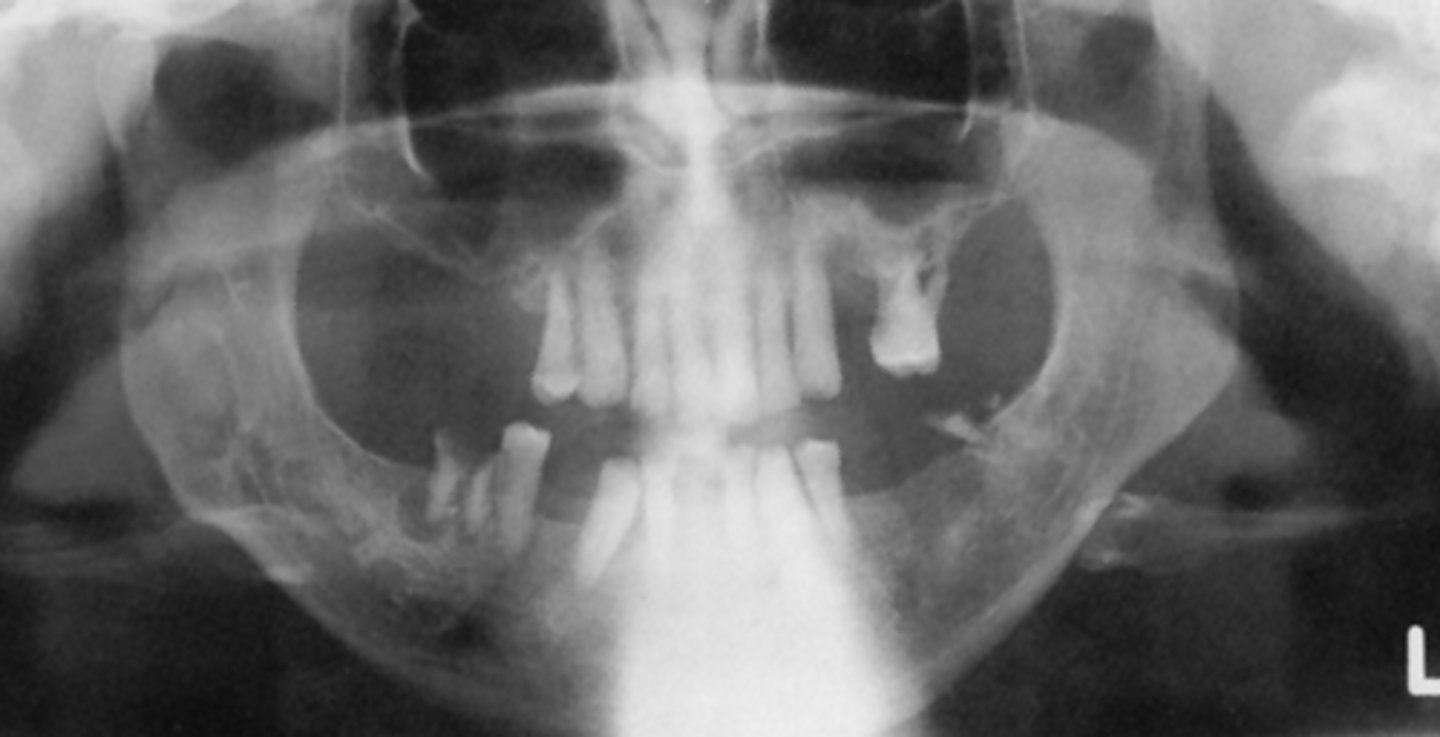

C) focal trough

What light needs to repositioned in order to gain the roots of the upper teeth?

A) mid-sagittal

B) Frankfort plane

What light needs to be repositioned in order to fix the flatness seen in this image?

A) up

The chin was slightly ___, resulting in this image

B) down

What light needs to be repositioned in order to fix the curve of the smile?

ghost of cervical spine

What does the light in the middle of this image represent?

patient moved

What is the cause of this break seen in the image?

What is the cause of this resultant image?

The curve of the image is slightly flat, which means the chin was slightly ___

body of hyoid

What is the structure circled in blue?

patient's chin was down

What is the problem that resulted in this image, relating to the occlusal plane?

If the pan image appeared too smiley, the patient's chin was too far ___ (image is just a placeholder and not necessarily related to this question)

If the pan image appeared too frowny, the patient's chin was too far ___ (image is just a placeholder and not necessarily related to this question)